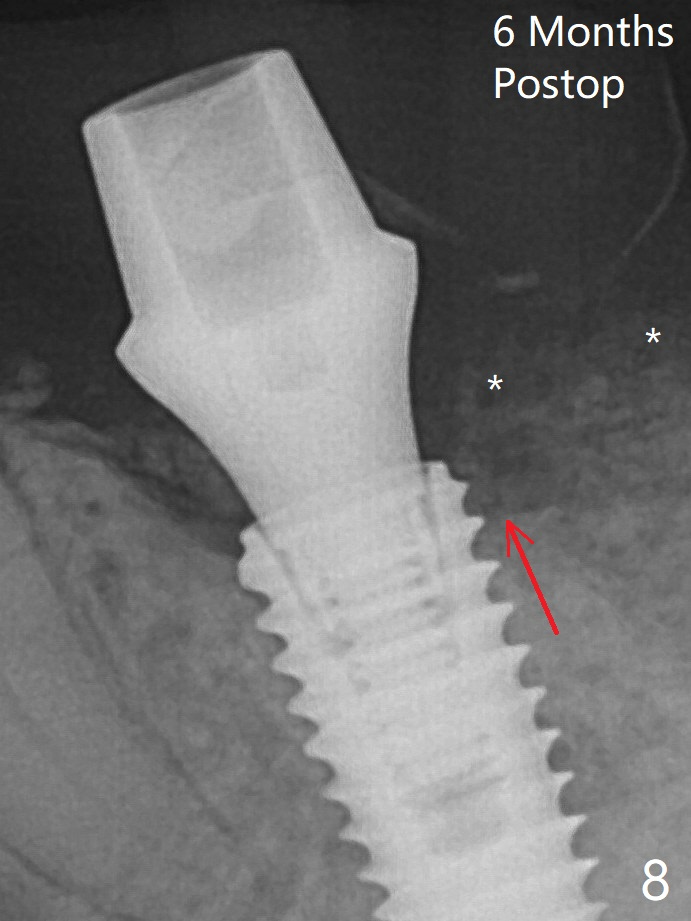

With all of measures taken (including periodontal dressing), the distal bone graft (Fig.8 *) is ~ 2 mm coronal to the crestal bone (red arrow) 6 months postop.  G: graft; <: septal crest.  In fact the abutment is incompletely seated.  The temporary crown is perforated.  The gingival cuff is erythematous.  A 6.8x5 mm healing abutment is installed.   When the patient returns for impression, take BW to determine whether the healing abutment contacts the crestal bone.